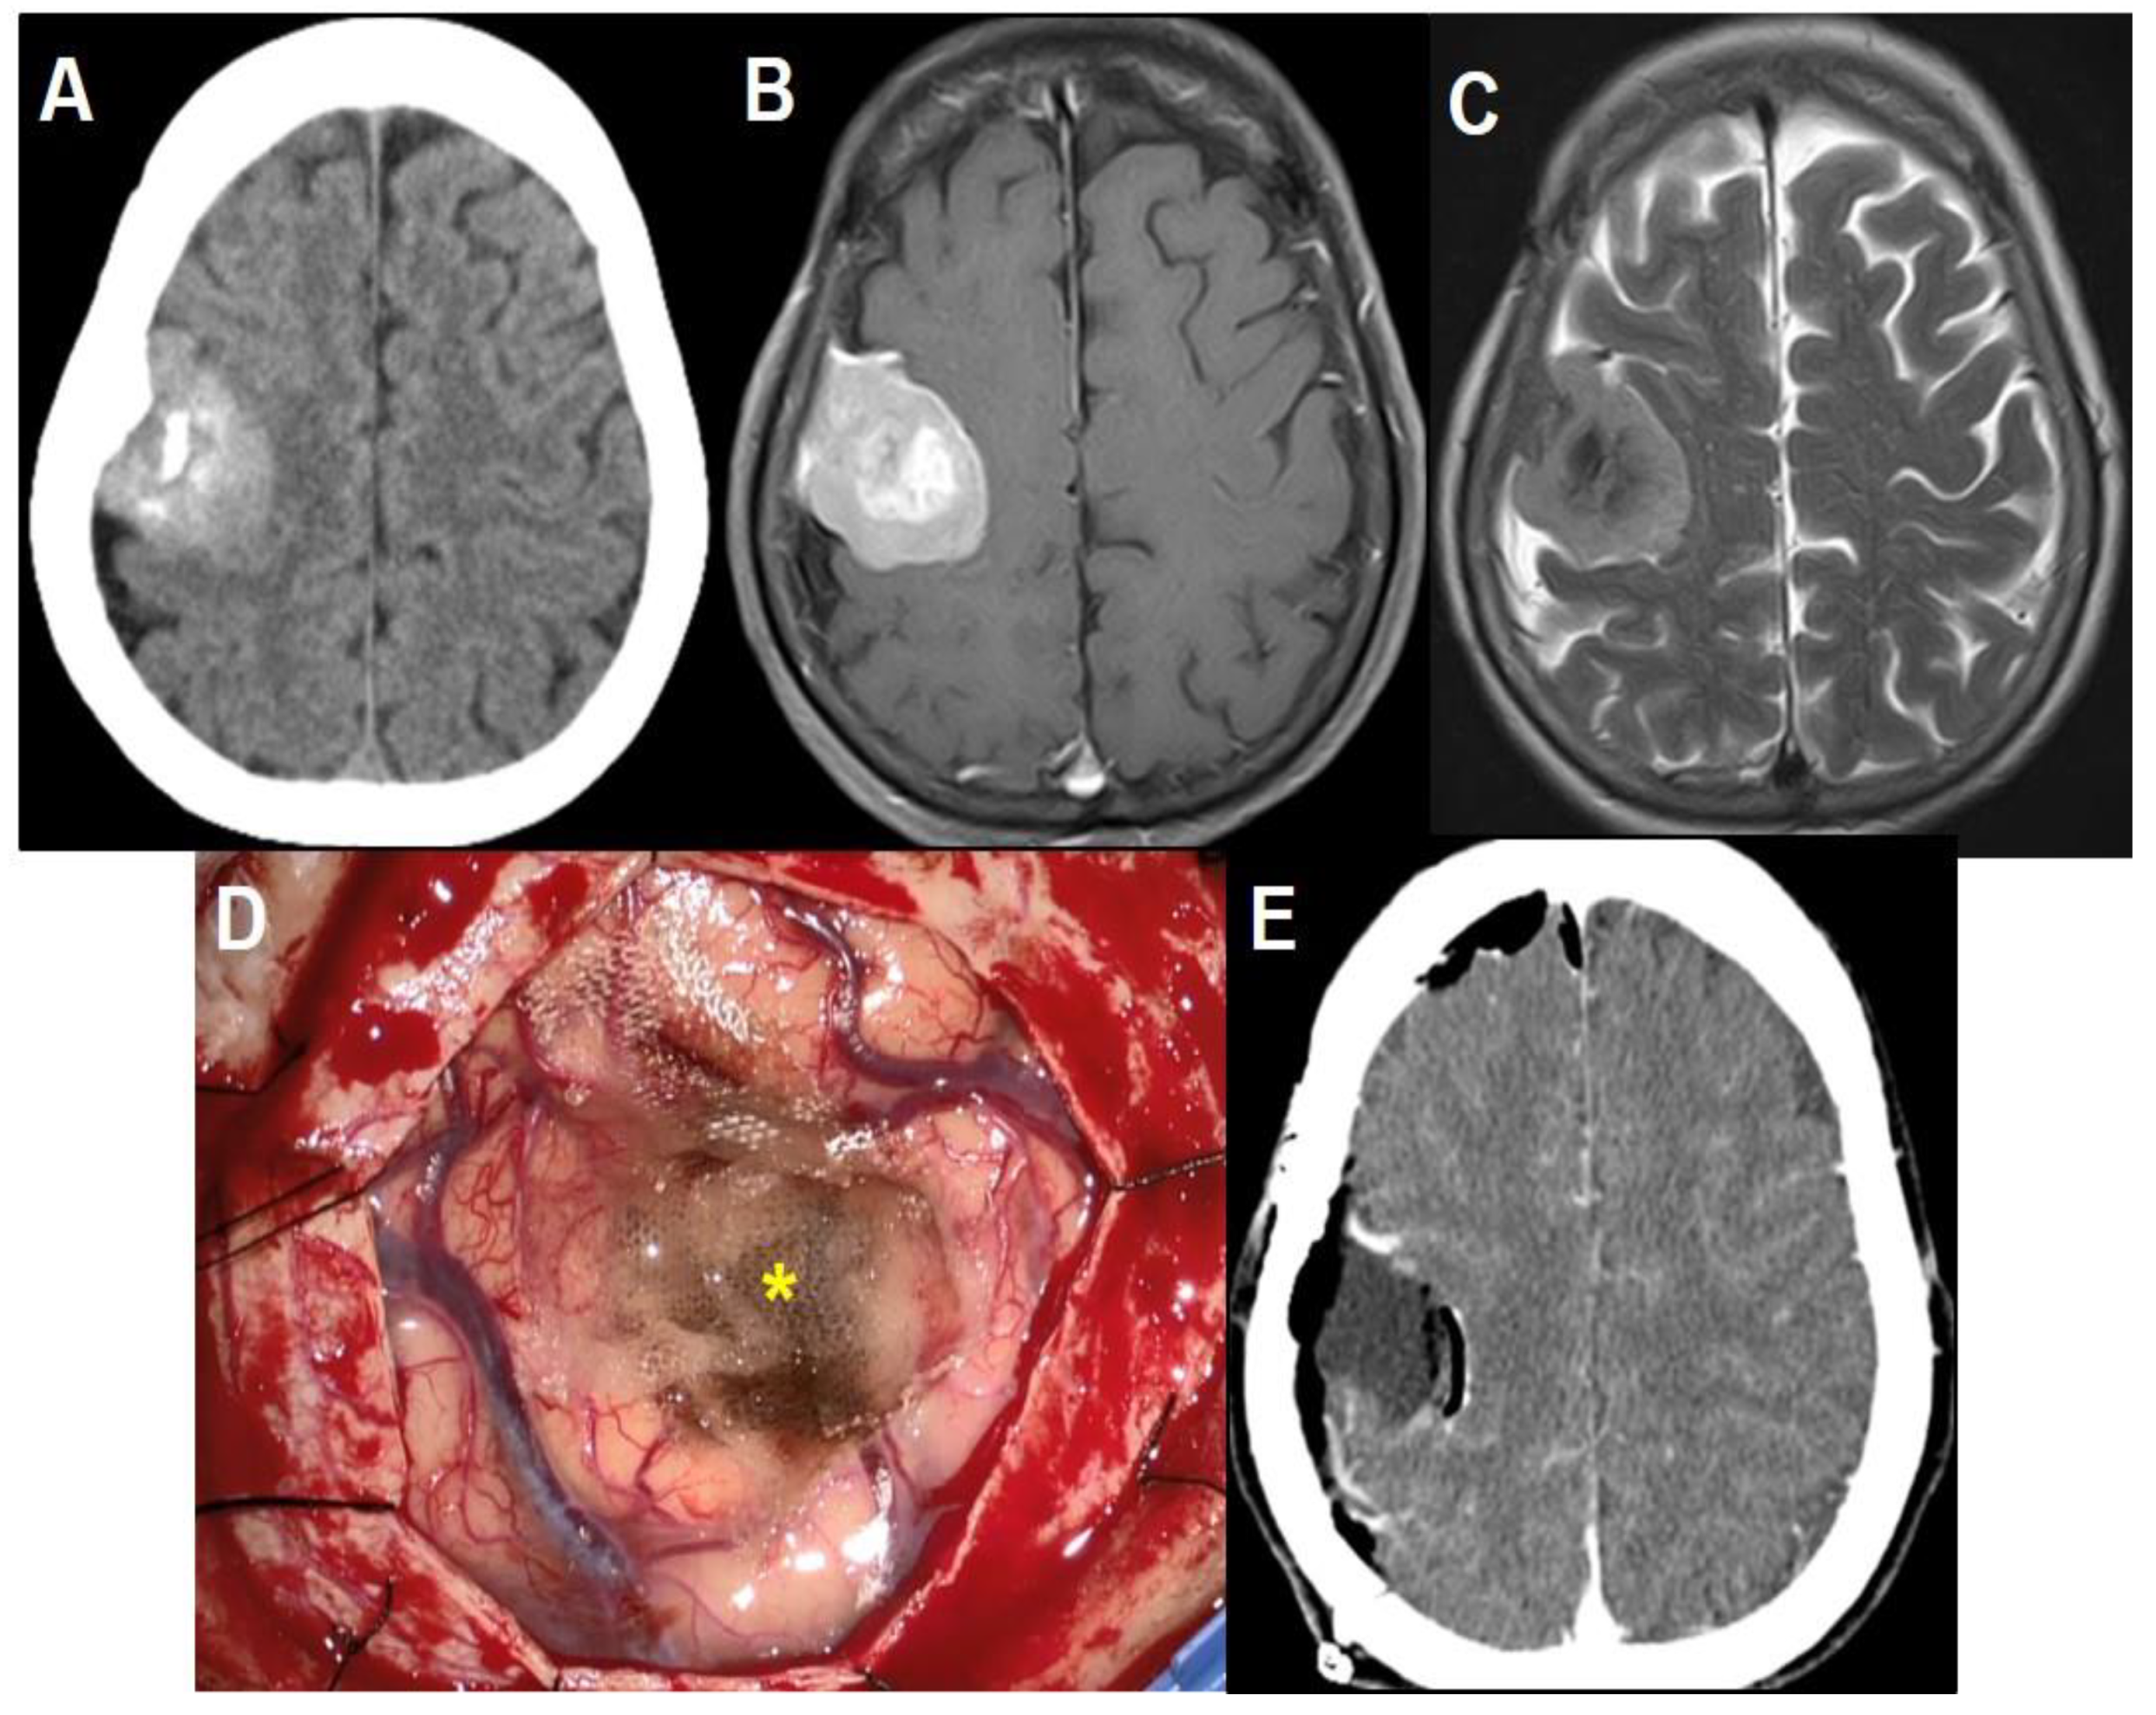

Six weeks after surgery, the patient complained of sudden left arm monoparesis. The CT scans and MR images revealed localized subdural fluid collection at the resection cavity with enhanced resection margin and perilesional edema, showing an iso-signal intensity of the cerebrospinal fluid (CSF) on T2-weighted and T1-weighted images. Diffusion restriction was not noticed (Figure 2A–C). There were no abnormal laboratory findings in the blood samples. The surgical wound was clean and well healed. After two weeks of conservative treatment with mannitol and steroids, the motor symptoms were completely recovered. The CT scans demonstrated decreased resection cavity size and marginal enhancement, but perilesional edema still existed (Figure 2D). Two weeks after the CT scans, the patient unfortunately presented with recurring left arm monoparesis and tingling sensations. The CT scans showed an increased amount of fluid in the cavity with perilesional edema (Figure 2E). After another two months of conservative treatment with prednisolone at 10 mg per day, she again fully recovered from the neurologic deficits. The CT scans showed decreased resection cavity size and perilesional edema (Figure 2F). Since then, the patient has had no specific neurologic deficits without specific medication. The latest MR images taken one year after operation revealed the complete disappearance of the fluid collection and perilesional edema with no recurrence (Figure 2G–I).

Figure 2. Time course of late-onset, localized subdural fluid collection in the resection cavity. (A) Gadolinium-enhanced T1-weighted and (B) T2-weighted axial MR images showing a subdural fluid collection at the resection cavity with an enhanced cavity margin and perilesional edema. (C) There was no diffusion restriction on the diffusion-weighted image. Brain CT scans taken after two weeks (D), four weeks (E), and three months (F) of conservative management show the spontaneous regression of the fluid collection and perilesional edema. Note that s temporary increase of the fluid collection was noted at discontinuing conservative therapy which was resolved after retreatment. (G–I). The latest MR images demonstrating the complete disappearance of the fluid collection without perilesional edema and recurrence.